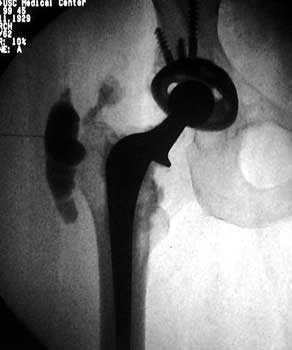

Normal arthrogram

Arthrographic evidence of looseningcontrast enters

abnormally widened interface Gruen zone 1 and 2

Arthrographic evidence of cup looseningcontrast enters

abnormally widened interface Gruen zone II and III